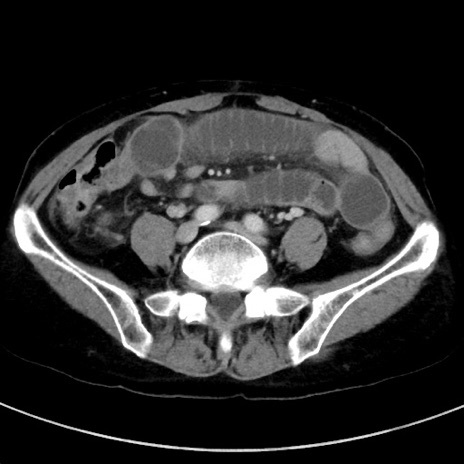

冠状断像

【症例】70歳代女性

【主訴】下腹部痛・嘔吐

【現病歴】2日前より腹痛あり。昨日嘔吐あり。症状改善しないため来院。

【既往歴】胃GISTに対して胃部分切除後。

【身体所見】BT 37.1℃、BP 128/77mmHg、腹部:平坦・軟、下腹部に圧痛あり。

【データ】WBC 10200、CRP 0.31